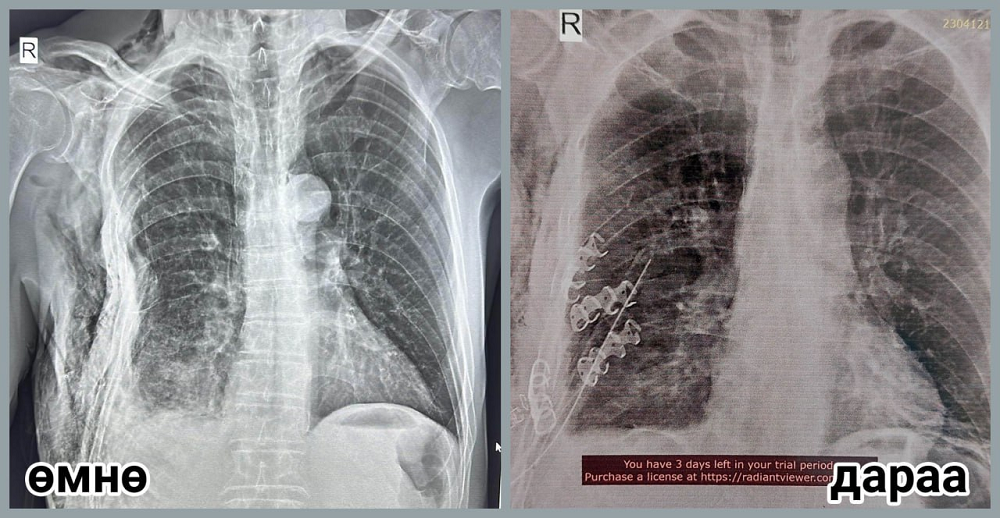

П.Баярсайхан эмчийн багт ГССҮТ-ийн мэс заслын их эмч С.Мөнхлхагва, резидэнт эмч Д.Мөнхзул, Мэс заслын нэгдсэн тасгийн сувилагч Б.Алтанцоож, жолооч С.Бүрэнтөгс нар багтсан бөгөөд тэд Булган аймгийн Нэгдсэн эмнэлгийн гэмтлийн их эмч Д.Алтангэрэл, мэс заслын их эмч Н.Энхжаргал, мэдээгүйжүүлгийн их эмч Т.Батдорж, мэс заслын сувилагч С.Ганчимэг, мэдээгүйжүүлгийн сувилагч Х.Хандсүрэн нартай хамтран өвчтөний хавирганы тогтворгүй хугарлыг бэхлэх мэс заслыг амжилттай хийсэн байна. Өвчтөний биеийн байдал сайжирч, тогтворжсон бөгөөд өдгөө аймгийнхаа Нэгдсэн эмнэлэгт мэс заслын дараах эмчилгээ хийлгэж байгаа юм.